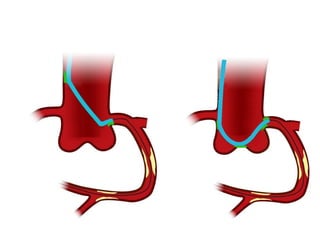

Assisted proximal then distal stenting

Stent advanced into   Extension advanced       Stent advanced into

proximal disease      through deployed stent   distal vessel with ease

= obstruction crossed

Assisted proximal thendistal stenting Stent advanced into Extension advanced Stent advanced into proximal disease through deployed stent distal vessel with ease = obstruction crossed